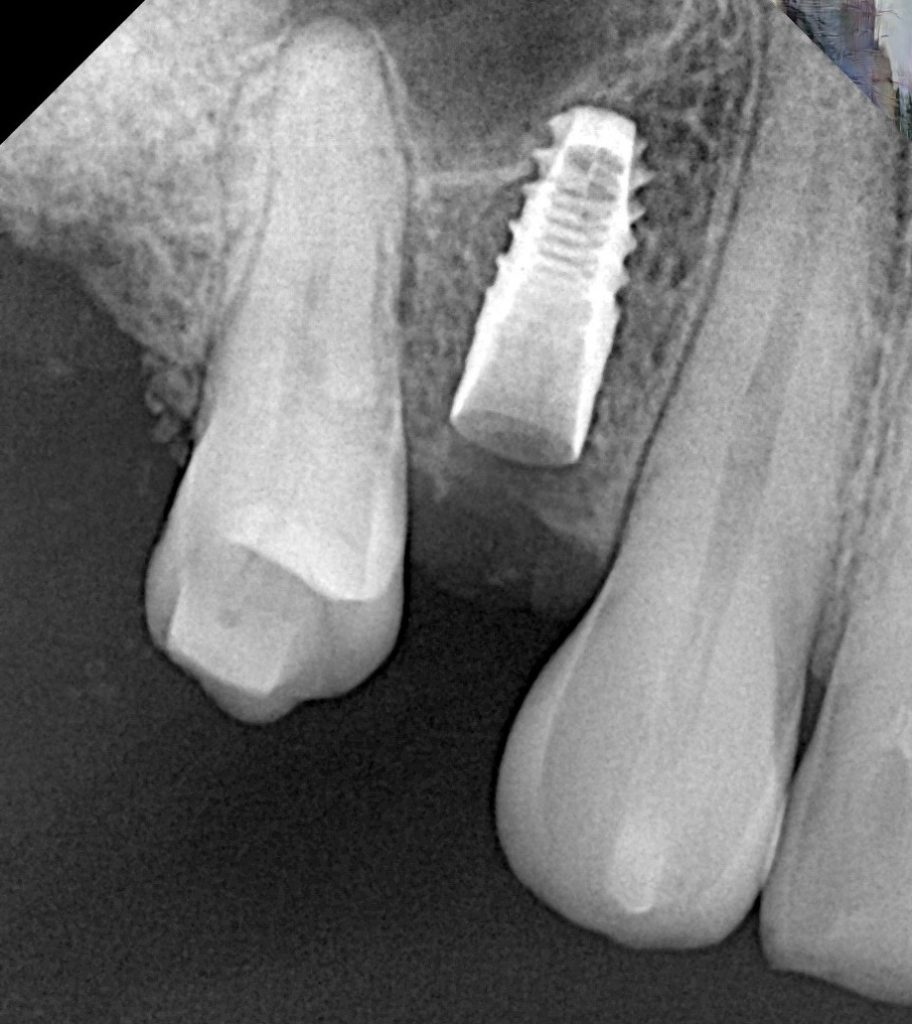

The patient presented with a missing maxillary first molar and reduced residual ridge height of approximately 6 mm (Fig 1). A CBCT scan revealed adequate bucco-palatal width and sinus floor proximity, indicating the need for a crestal (indirect) sinus lift rather than a lateral window procedure.